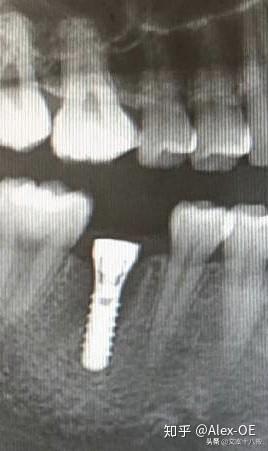

總的來說,步驟有點多但每步都不復(fù)雜,打了麻藥后手術(shù)全程沒什么痛感。選擇了瑞士ITI植體,2018年7月6日下午把種植體,即人造牙根植入了牙槽骨內(nèi),等待愈合三五個月后再匹配牙冠,完成了整個植牙流程。

2018年7月6日,下午先拍了CT,很小劑量的輻射。主任方醫(yī)師說我的情況符合植牙條件,骨量也沒有問題,接下來安排了方案并開始手術(shù),由方醫(yī)師操刀,整個手術(shù)由3個醫(yī)生共同完成。用消毒水漱口兩分鐘后,躺在那個椅子上,燈光刺眼,消毒棉花在口腔周圍一圈一圈得涂,鼻子上都涂了。身上蓋了做手術(shù)的綠布(這個布有名稱嗎?),只露出口腔。因為眼睛也在綠布底下,所以手術(shù)全程看不到醫(yī)生用過哪些工具,只能想象醫(yī)生在干什么,做了麻醉感覺不到切開牙齦,鉆孔的疼痛,但是植入牙體是有感覺的,畢竟那么大的東西硬生生的塞了進(jìn)去,從醫(yī)生手肘的顫動知道這牙題塞進(jìn)牙槽骨挺費勁的。術(shù)前忘記看時間了,估計今天整個過程開始到結(jié)束大概40分鐘,40分鐘內(nèi)還包括了十幾分鐘的醫(yī)生的清潔準(zhǔn)備工作。沒有什么不適,不過醫(yī)生有一會兒手碰巧壓住鼻子上面的綠布了,就只能用嘴呼吸了。我也沒提醒醫(yī)生覺得很快就過去了,醫(yī)生說有任何不適可以隨時叫停。(因為在清潔的綠布底下,隨意抬手示意會造成污染,能不停就別停了,真的有不適吱聲就行)沒告訴他,大概憋了快一分鐘氣覺得種牙還沒有拔牙痛,只是長時間張著嘴比較難受,術(shù)后拍片醫(yī)生說果不錯,配了消炎藥和漱口水,臉貼著冰袋回去了,一周后拆線?,F(xiàn)在已經(jīng)過去8個小時了,麻醉藥也過了,有少量滲血,但疼痛感十分輕微。植牙回去以后,怕麻醉藥過去后疼,下午2點植入后敷冰袋到了晚上8點。那時候確實感覺到疼,不過是輕微而持續(xù)的疼,并且這種輕微的疼大概持續(xù)了四天,術(shù)后配的藥也差不多吃完,那之后就沒事了。